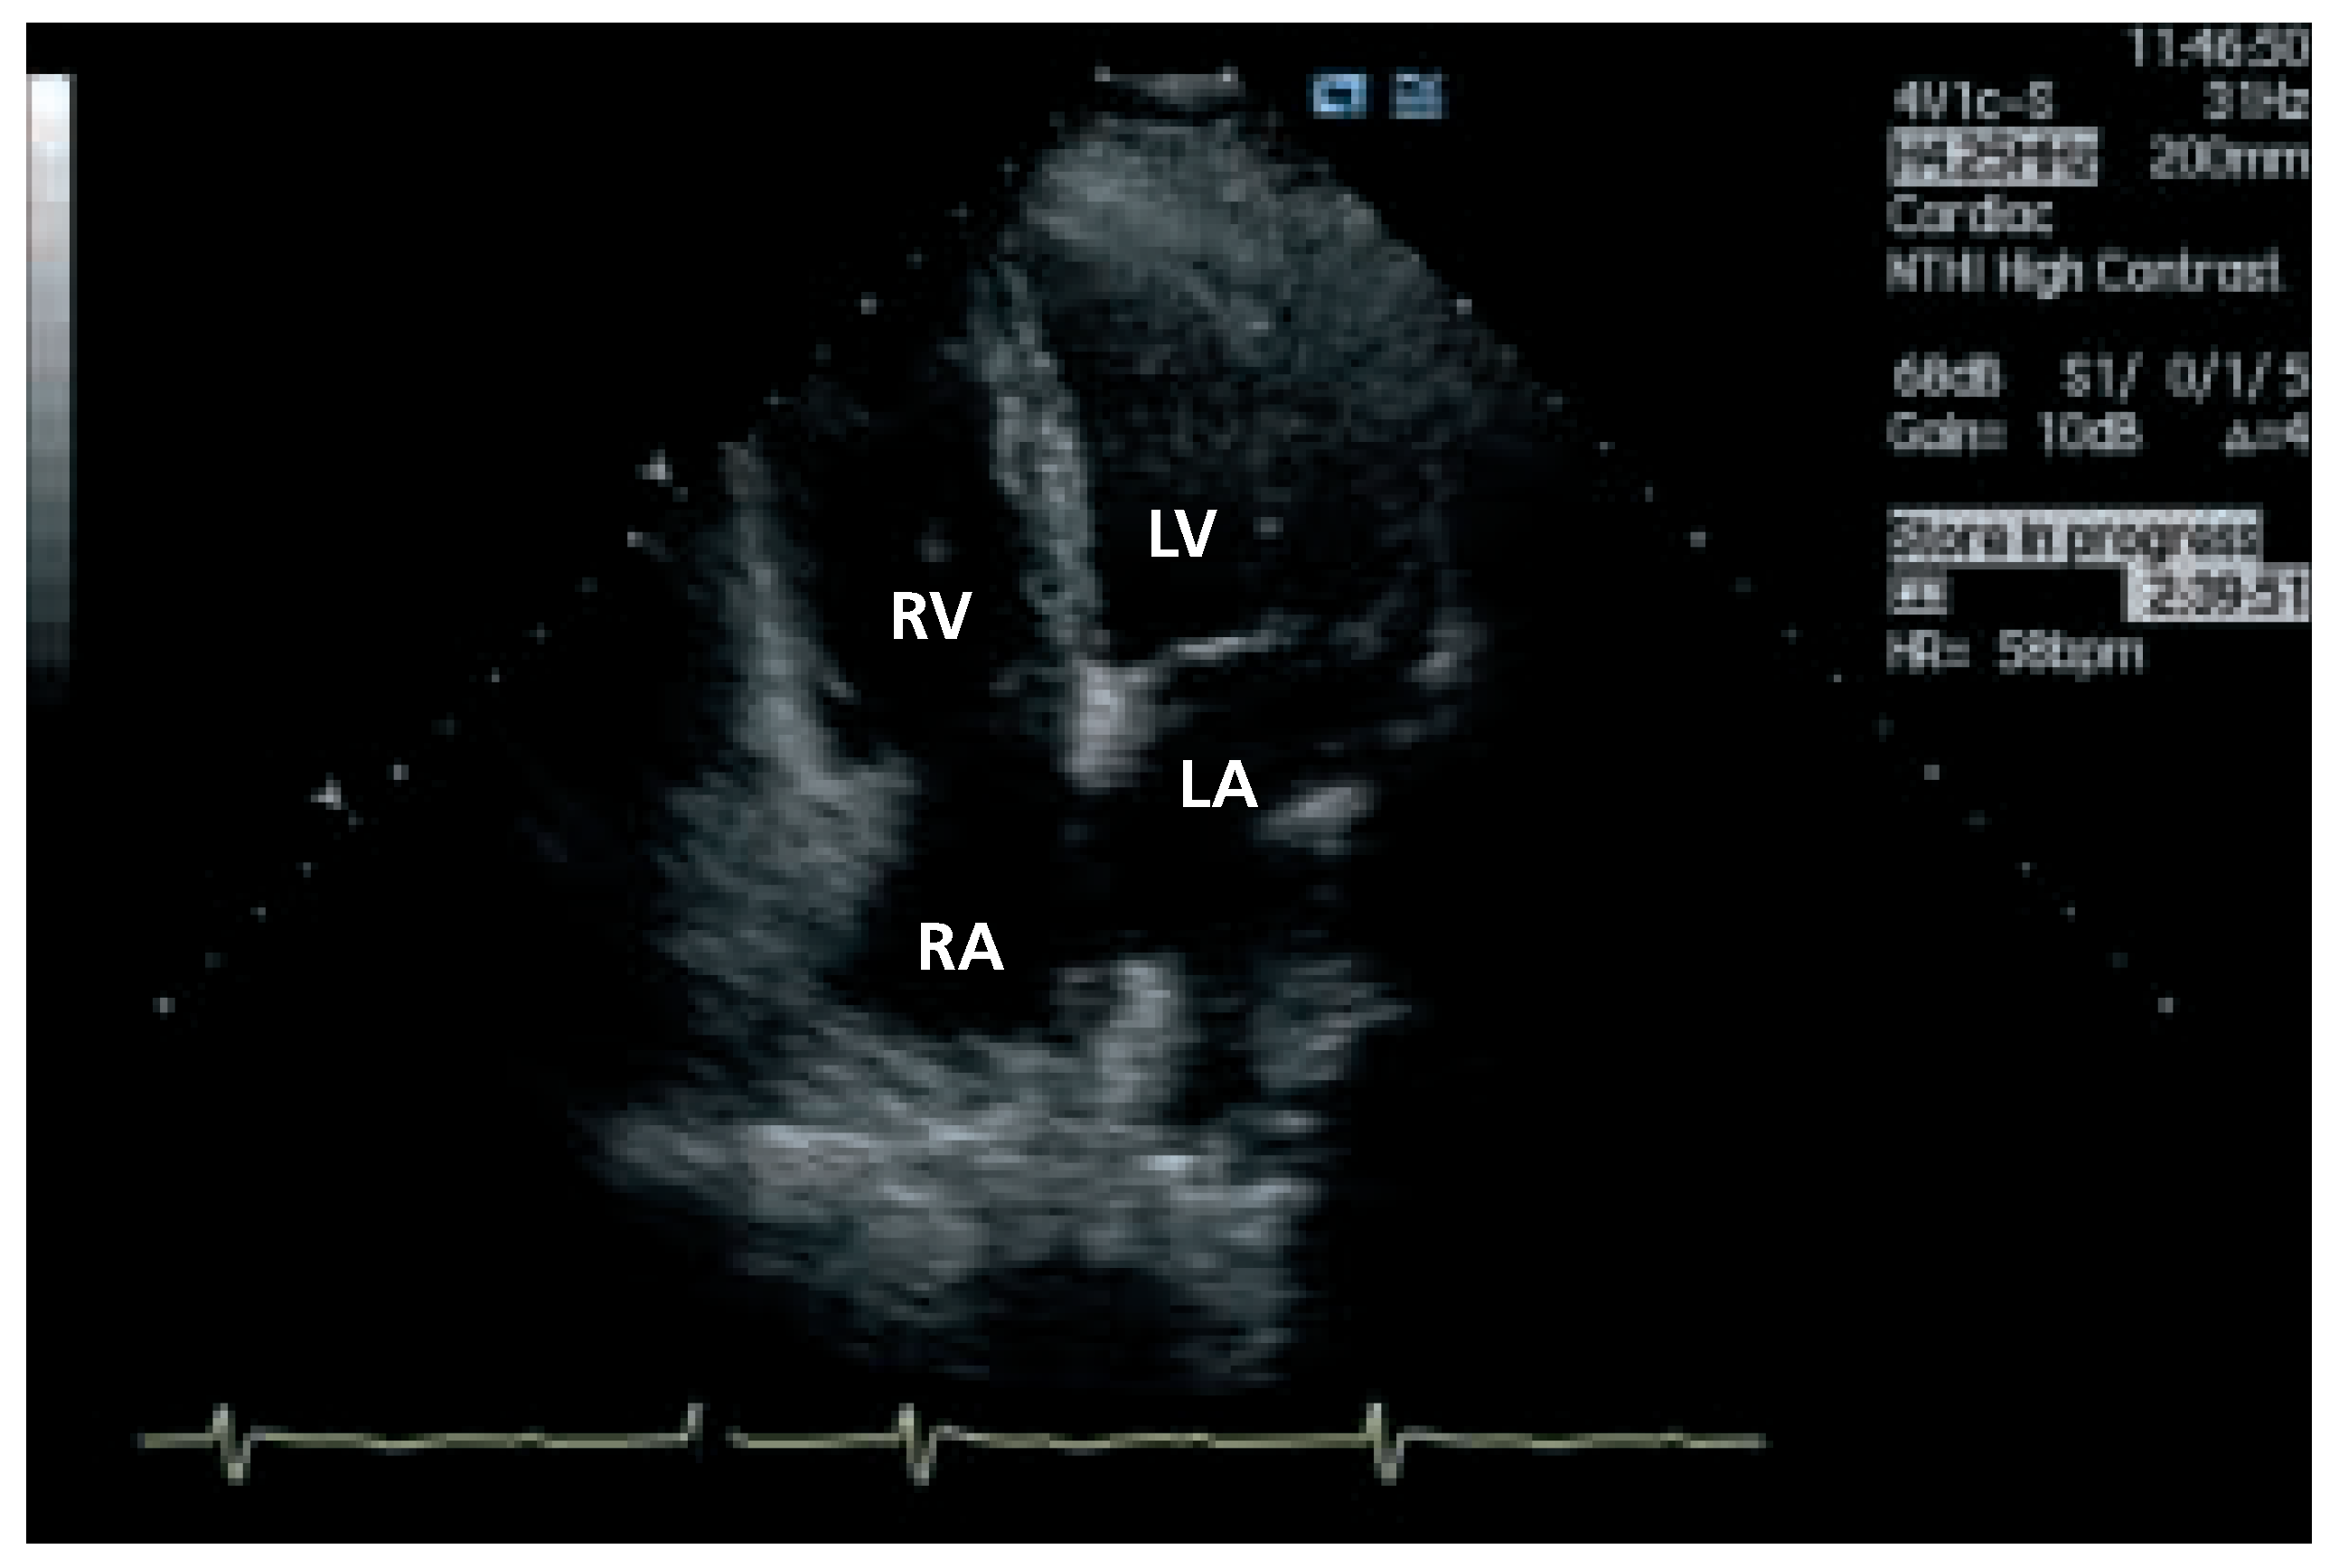

Transthoracic echocardiography (Figure 4 and Figure 5) is not normal and shows right heart overload with dilatation of the right sided cavities, elevated pulmonary artery pressure (estimated systolic pulmonary pressure about 56 mm Hg) and normal sized left ventricle. The reason for the dilatation of the right sided cavities was found in the presence of two secundum atrial septal defects with predominantly left-to-right shunting. Transoesophageal echocardiography was not performed.

Figure 4. Echocardiography: 4 chamber view with enlarged right ventricular size. RA = right atrium; LA = left atrium; RV = right ventricle; LV = left ventricle.